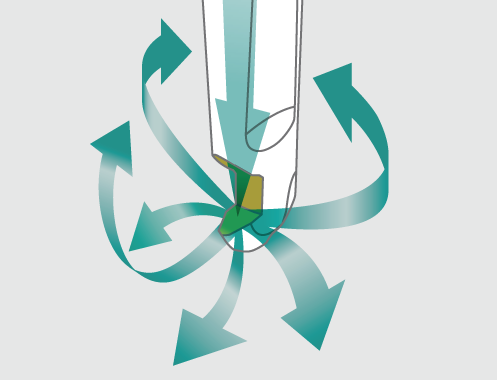

Las piezas de mano Perio-Mate se utilizan en el tratamiento de bolsas periodontales y periimplantitis. En los procedimientos de higiene oral, resulta fundamental evitar lesiones en los tejidos blandos y en las superficies de la raíz dentro de las delicadas bolsas periodontales. El pulverizador de agua ultrafino de Perio-Mate y su Polvo con base de glicina se aúnan para eliminar con delicadeza la película biológica de las bolsas periodontales en tan sólo 20 segundos. Gracias a los años de experiencia acumulados en el análisis de la dinámica de fluidos para desarrollar su tecnología de turbinas, NSK ha concebido un sistema de pulverización seguro y tremendamente eficiente que permite una eliminación precisa y rápida de la placa bacteriana presente en las zonas subgingivales.

Los análisis sobre dinámica de fluidos realizados por NSK a lo largo de los años han servido para desarrollar una tecnología de turbinas que tiene siempre muy presente la capacidad de maniobra del facultativo en un espacio tan limitado como es el interior de la bolsa.